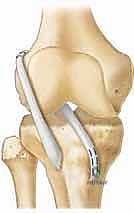

شكل 6: تمرير الطعم الوتري الجديد داخل الركبة بمهارة عالية. يتم سحب الطعم عبر الأنفاق العظمية أو حولها ليتخذ الوضع التشريحي الدقيق للرباط الصليبي الأصلي.

شكل 7: التثبيت النهائي للطعم الوتري. يتم استخدام أدوات تثبيت متطورة (مثل الأزرار المعلقة أو المسامير القابلة للامتصاص) بعيداً عن الغضاريف النمائية لضمان ثبات الرباط الجديد والسماح له بالالتئام.

- تمرير وتثبيت الطعم: يتم إدخال الرباط الجديد وتثبيته بقوة باستخدام أزرار معدنية أو مسامير طبية خاصة لا تعيق النمو.